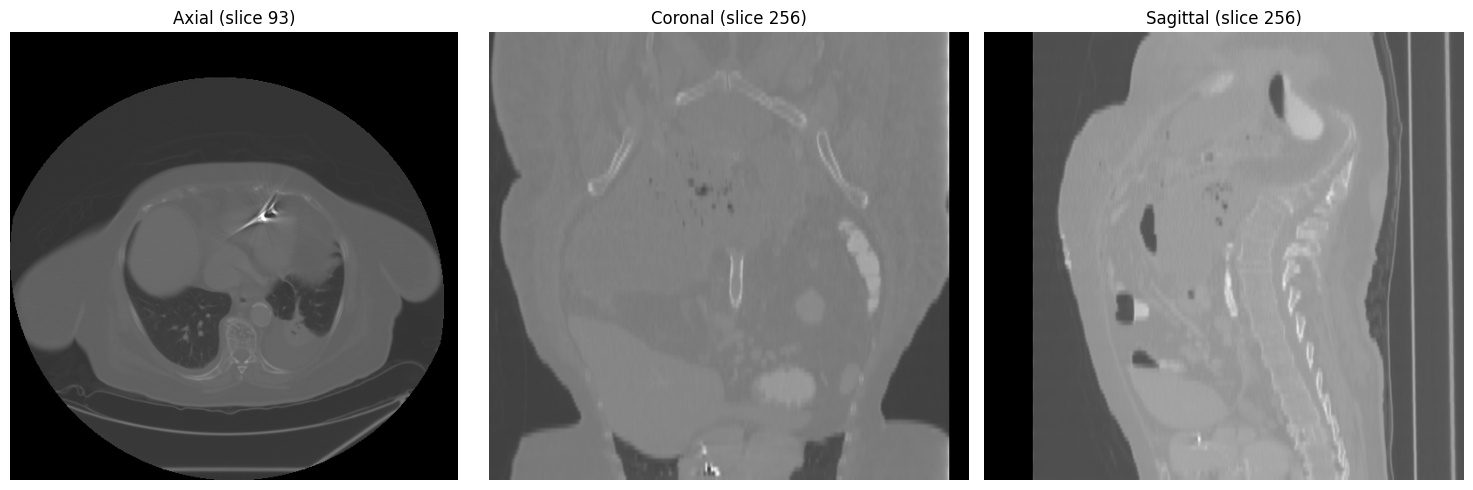

Three-view overview at mid-chest level (axial, coronal, sagittal):

Axial, coronal, and sagittal views at mid-chest